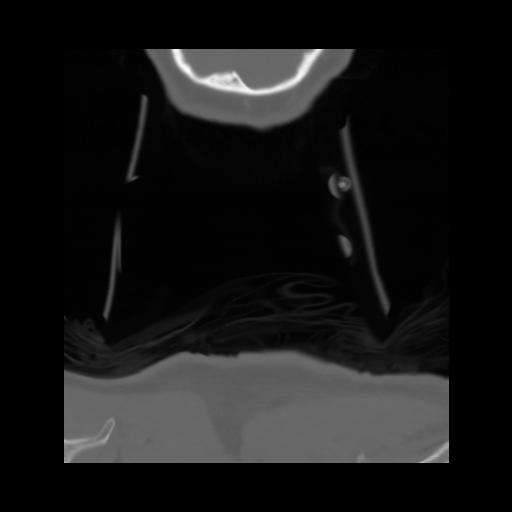

13 P.BLANDAS,,Coronal,2.000,P.BLANDAS,Coronal,